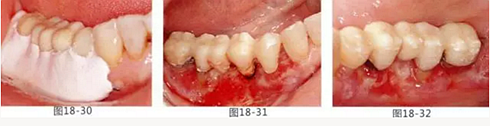

圖18-30 在頰側(cè)以及舌側(cè)涂上牙周塞治劑。然后將咬合面少許削除。

圖18-31 手術完成1周的頰側(cè)面照。

圖18-32 同部位的舌側(cè)面照。